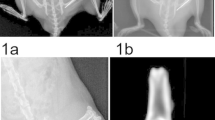

Immunohistochemical findings

The immunohistochemical findings are summarized in Table 3. The presence of BMP-4, 6, 7, and 9 was observed in all IM samples. Representative immunohistochemical images are shown in Fig. 1 (Case 3, femur) and Fig. 2 (Case 4, tibia). Immunolocalization of BMP-4, 6, 7, and 9 was observed in blood vessels (Figs. 1a, b, 2a, b) and in fibroblasts (Figs. 1c, d, 2c, d). These findings were observed in all IM samples. Immunolocalization of BMP-4, 6, 7, and 9 was also observed in the bone within the IM in one sample in which osteogenesis inside the IM was observed (Fig. 2e, f). Finally, immunostaining of human bone tissue as a positive control demonstrated positive immunoreactivity for BMP-4, 6, 7, and 9 (Fig. 3).

Representative immunohistochemical images of the induced membrane (Case 3, femur) a blood vessel, low-power field, b blood vessel, high-power field, c fibroblast, low-power field, d fibroblast, high-power field. The arrows indicate immuno-positive staining. BMP bone morphogenetic protein, H/E hematoxylin and eosin